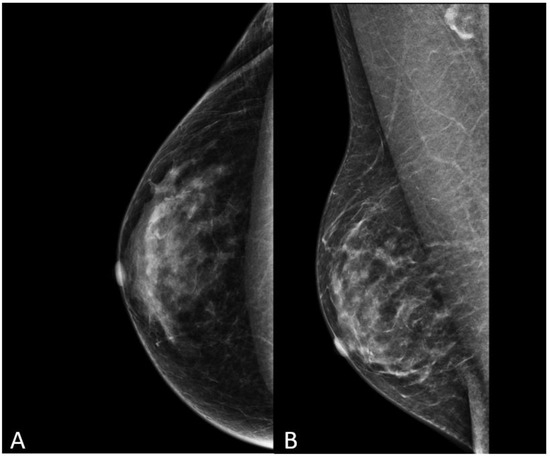

Figure 9.

Mammography in cranio-caudal (A) and medio-lateral oblique (B) views in a 52-year-old transgender woman after 5 years of hormone therapy.